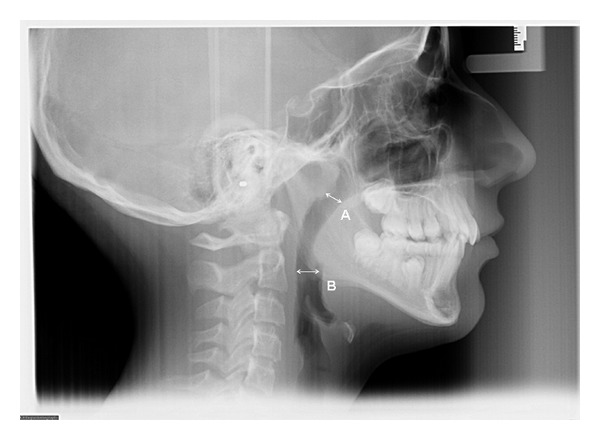

Objectives. The primary objectives of this retrospective study were first to compare the upper and lower pharyngeal airway spaces between orthodontic patients with and without maxillary constriction and second to evaluate the effect of rapid maxillary expansion (RME) on these airway spaces. A secondary objective was to compare the mode of breathing between groups. Materials and Methods. The experimental (RME) group consisted of 30 patients (mean age, 14.2 ± 1.3 years, 16 boys and 14 girls) with maxillary constriction who were treated with hyrax-type RME. The control group comprised the records of age- and gender matched patients (mean age, 13.8 ± 1.5 years, 16 boys and 14 girls) with no maxillary constriction but requiring nonextraction comprehensive orthodontic treatment. Cephalometric measurements in the sagittal dimension of upper and lower airway spaces for the initial and final records were recorded. Mode of breathing and length of treatment were also compared. Results. The sagittal dimension of the upper airway increased significantly in the RME group (mean = 1.3 mm) compared to the control group (mean = 0.5 mm), P = 0.016. However, there was no significant difference in the lower pharyngeal airway measurement between the RME group (mean = 0.2) and the control group (mean = 0.4), P = 0.30. There was no significant difference with respect to mode of breathing between the two groups (P = 0.79). Conclusion. Rapid maxillary expansion (RME) during orthodontic treatment may have a positive effect on the upper pharyngeal airway, with no significant change on the lower pharyngeal airway.